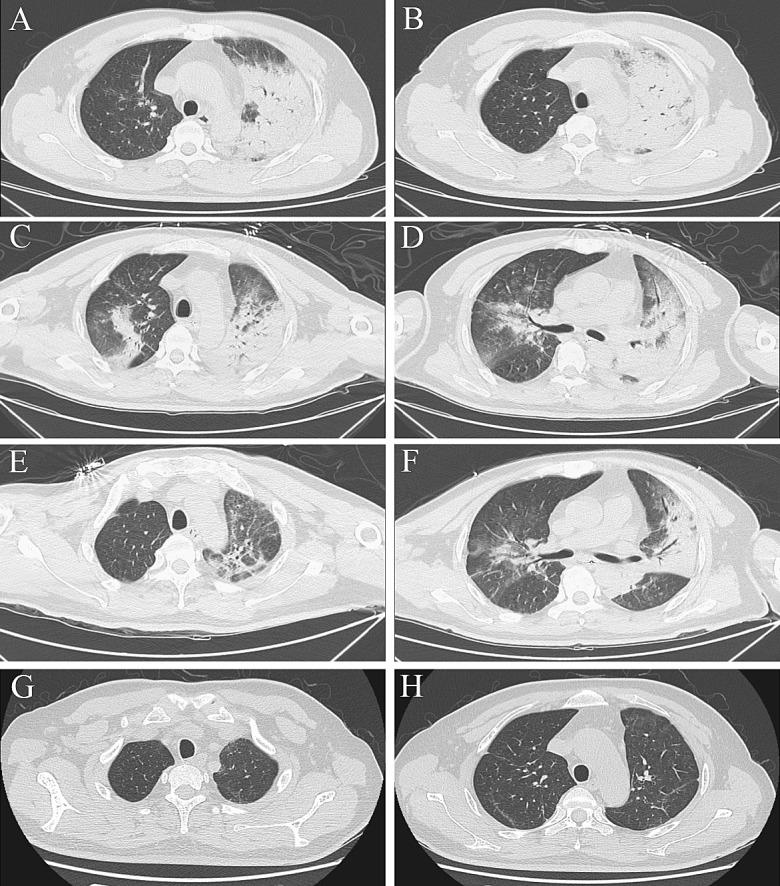

Frequent symptoms included chills and remittent fever (100%), cough and hypodynamia (100%), and headache and myalgia (77.8%). All patients were severe psittacosis pneumonia developed respiratory failure, accompanied by sepsis in 6/9 patients. mNGS takes 48-72 h to provide the results, and help to identify diagnosis of psittacosis. Laboratory data showed normal or slightly increased leucocytes, neutrophils, and procalcitonin but high C-reactive protein levels. Computed tomography revealed air-space consolidation and ground-glass opacity, which began in the upper lobe of one lung, and spread to both lungs, along with miliary, nodular, or consolidated shadows. One patient died because of secondary infection with Klebsiella pneumoniae, while the other eight patients experienced complete recoveries.

常见症状包括寒战和间歇热(100%)、咳嗽和乏力(100%)以及头痛和肌痛(77.8%)。所有患者均为严重鹦鹉热肺炎导致呼吸衰竭,其中 6/9 例患者伴有脓毒症。mNGS 需要 48-72 小时才能提供结果,并有助于明确鹦鹉热的诊断。实验室数据显示白细胞、中性粒细胞和降钙素原正常或略有增加,但 C 反应蛋白水平较高。计算机断层扫描显示气腔实变和磨玻璃影,始于一肺上叶,然后蔓延至双肺,并伴有粟粒状、结节状或实变阴影。1 例患者因感染肺炎克雷伯菌而死亡,而其他 8 例患者完全康复。